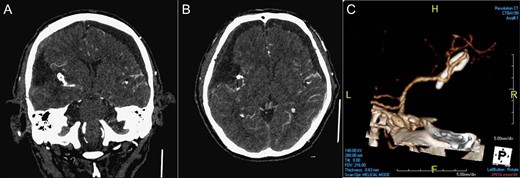

Brain magnetic resonance imaging (MRI) and MR angiography (MRA) revealed a large extraaxial well-circumscribed mass lesion with some calcification/hemorrhage in the right frontal–temporal convexity, abutting the skull bone, measured ~7.7 cm in maximal diameter. Post-contrast study showed good and somewhat heterogeneous enhancement with dural tail sign. Incidentally, a suspicious small aneurysm in bifurcation of the right MCA was found (Fig. 1). CT angiography (CTA) of brain was further arranged which demonstrated a wide-based saccular aneurysm in bifurcation of the right MCA, ~4.7 mm in size, abutting the tumor with dome tilting laterally, anteriorly and inferiorly (Fig. 1). Due to the significant mass effect of the brain tumor and the progressive neurological decline of the patient, surgical resection of the tumor and clipping of the aneurysm in one operation was planned.

Pre-operative imaging. Axial T1 weighted image post gadolinium enhancement (A), coronal T1 weighted image post gadolinium enhancement (B) showing a large extraaxial well-circumscribed mass lesion in the right frontal–temporal convexity, abutting the skull bone with good enhancement and dural tail sign (black arrow in Fig. 1A). MRA (C) showing a suspicious small aneurysm in bifurcation of the right middle cerebral artery (white arrow). CTA of brain coronal view (D), axial view (E), 3D reconstruction (F) showing a wide-based saccular aneurysm in bifurcation of the right middle cerebral artery abutting the tumor with dome tilting laterally, anteriorly and inferiorly.

The patient recovered well after surgery and can achieve independent life. His early post-operative CTA of brain (Fig. 3) showed the complete removal of the tumor and the complete surgical clipping of the aneurysm without residual lesions. Post-operative adjuvant radiotherapy was arranged since intracranial solitary fibrous tumor/hemangiopericytoma grade 2 is locally aggressive.

Post-operative imaging. CTA of brain coronal view (A), axial view (B), 3D reconstruction (C) showing the complete removal of the tumor and the complete surgical clipping of the aneurysm without residual lesions.